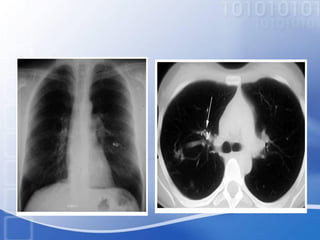

• The evaluation of hemoptysis involves a careful

history, physical examination, and a chest

radiograph. Initial studies also include a

complete blood count.

• The evaluationof hemoptysis involves a careful history, physical examination, and a chest radiograph. Initial studies also include a complete blood count. • In the vast majority (90%) of cases the source of the bleeding is the bronchial circulation. • Massive hemoptysis may be due to active TB, prior TB, bronchiectasis, mycetoma, Tight mitral stenosis, and lung cancer. (Corder, 2003 )